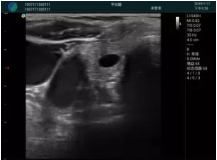

清晰顯示孕囊,通過軟件包計算孕齡7w+6d

M20實時引導(dǎo),術(shù)中清晰顯示孕囊被破壞和抽吸針的過程,清晰顯示吸引針

抽吸結(jié)束后縱切子宮,孕囊已被完全抽吸,未見明顯殘留

橫切子宮,發(fā)現(xiàn)右側(cè)宮腔靠近宮角處有少許脫模樣殘留

M20引導(dǎo)下,抽吸針找到右側(cè)宮角處再次清掃

二次抽吸后再次進行超聲檢查,宮腔未見殘留,宮腔線清晰顯示